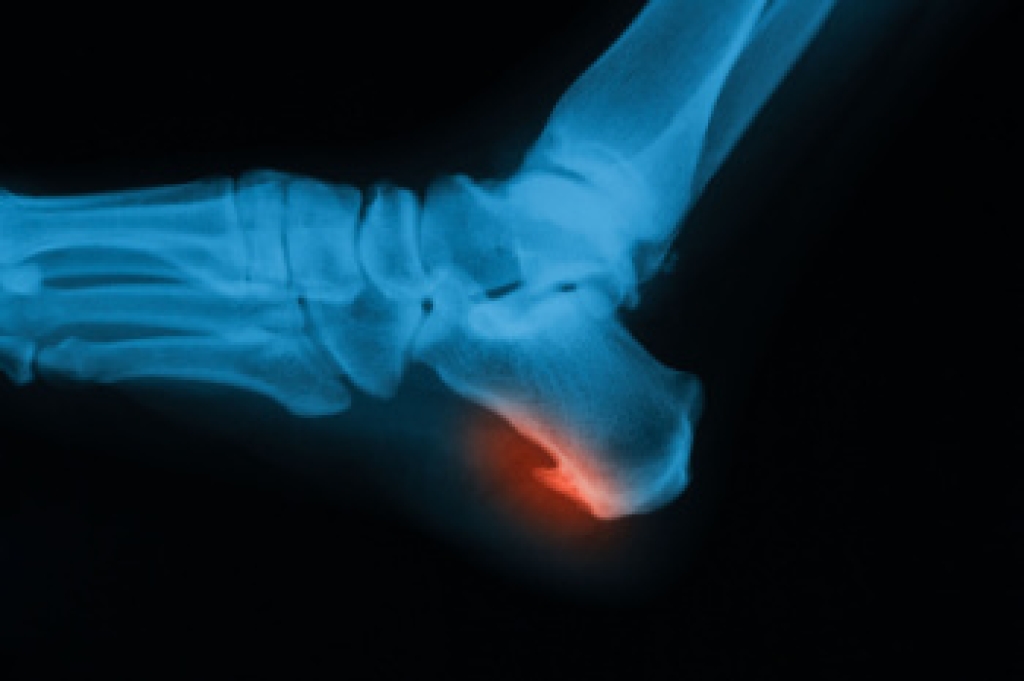

Wound care is an important medical specialty focused on the treatment and management of acute and chronic wounds, especially in the feet where healing can be more complex. Patient preferences on wound care may reflect attitudes and beliefs, possibly based on education. Some types of foot wounds may develop from pressure, injury, poor circulation, or complications related to conditions such as diabetes. Risk factors include reduced blood flow, nerve damage, infection, and prolonged pressure on certain areas. Common types of foot wounds include ulcers, cuts, and slow healing sores that can worsen without proper care. A podiatrist plays a key role by providing debridement, infection control, and pressure relief to promote healing. Early treatment helps prevent serious complications. If you have any type of foot wound, it is suggested that you promptly consult a podiatrist who can take your preferences into account and offer appropriate treatment solutions.

While it may not seem apparent with small ulcers on the foot, for diabetics, any size ulcer can become infected. Diabetics often also suffer from neuropathy, or nerve loss. This means they might not even feel when they have an ulcer on their foot. If the wound becomes severely infected, amputation may be necessary. Therefore, it is of the upmost importance to properly care for any and all foot wounds.

The best way to care for foot wounds is to prevent them. For diabetics, this means daily inspections of the feet for any signs of abnormalities or ulcers. It is also recommended to see a podiatrist several times a year for a foot inspection. If you do have an ulcer, run the wound under water to clear dirt from the wound; then apply antibiotic ointment to the wound and cover with a bandage. Bandages should be changed daily and keeping pressure off the wound is smart. It is advised to see a podiatrist, who can keep an eye on it.